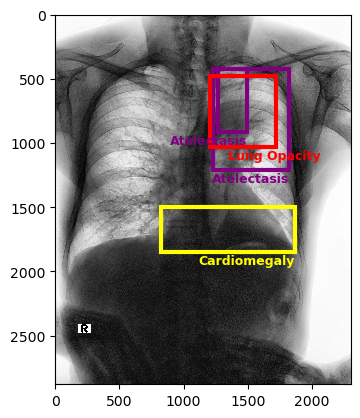

The VinDr-CXR dataset includes 15,000 images within its training set, with labels manually defined by a team of radiologists. Figure 3 presents sample images from this dataset. The dataset includes 22 local labels represented by bounding boxes surrounding abnormalities, and six global labels denoting detected diseases. The images are provided in the Digital Imaging and Communications in Medicine (DICOM) format, accompanied by relevant DICOM tags such as patient sex and age. Primarily consisting of posterior-anterior (PA)-view chest X-rays, the dataset excludes non-relative X-rays from other body parts [23].